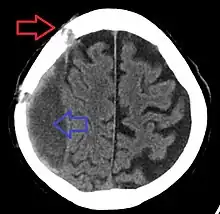

| Subdural hematoma as marked by the arrow with significant midline shift | |

Subdural hematomas occur most often around the tops and sides of the frontal and parietal lobes.[3][2] They also occur in the posterior cranial fossa, and near the falx cerebri and tentorium cerebelli.[3] Unlike epidural hematomas, which cannot expand past the sutures of the skull, subdural hematomas can expand along the inside of the skull, creating a concave shape that follows the curve of the brain, stopping only at dural reflections like the tentorium cerebelli and falx cerebri.

On a CT scan, subdural hematomas are classically crescent-shaped, with a concave surface away from the skull. However, they can have a convex appearance, especially in the early stages of bleeding. This may cause difficulty in distinguishing between subdural and epidural hemorrhages. A more reliable indicator of subdural hemorrhage is its involvement of a larger portion of the cerebral hemisphere. Subdural blood can also be seen as a layering density along the tentorium cerebelli. This can be a chronic, stable process, since the feeding system is low-pressure. In such cases, subtle signs of bleeding—such as effacement of sulci or medial displacement of the junction between gray matter and white matter—may be apparent.